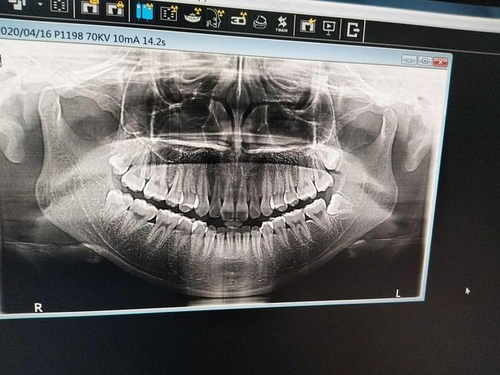

如果是拔其它牙齿,那在口腔诊所就可以拍片,但是拔智齿的时候需要拍医学x光片,是需要到医院进行拍片的。通过x光片可以了解牙根的具体位置和分布状态,能有效减少意外状况的发生。